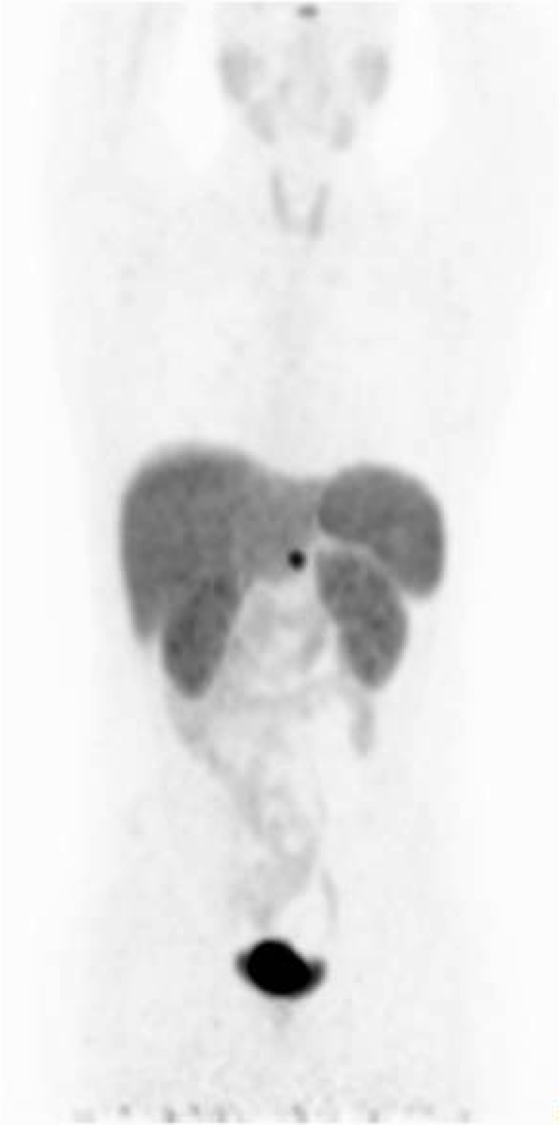

Male, 20 y/o, with hypoglycemia operated on twice of insulinoma. Asymptomatic, MR showed a possible lesion in the pancreas. It was requested PET-CT withGa68 DOTANOC. A nodule is seen in the body of pancreas, 15 mm, SUV max of 29 (cross in transaxial slices). The upper CT slice shows the arterial phase with nodular enhancement and at the bottom the venous phase, (cross both in PET and CT images).